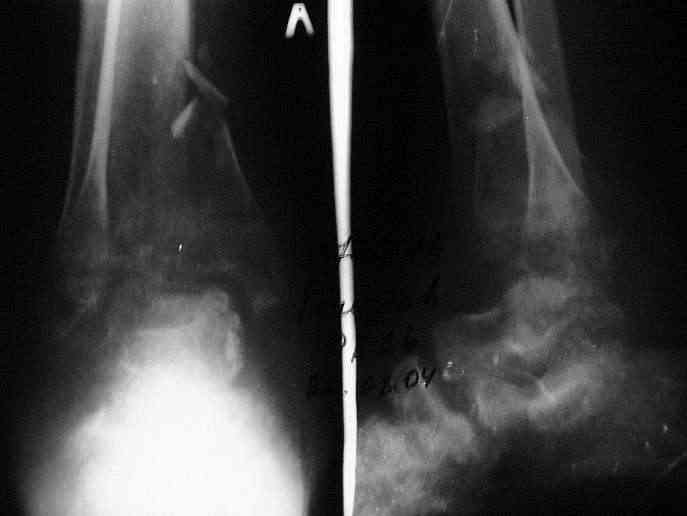

Мной был демонтирован АВФ, удалены все спицы. Больной некоторое время лечился консервативно (шина Белера, антибиотики, перевязки). По заживлению и купировании гнойно-воспалительного процесса была произведена осткрытая репозиция, накостный остеосинтез 1/3 трубчатой пластиной.Такой вариант был принят из-за жуткого остеопороза и отказом больного от предложенного артродезирования голеностопного сустава сразу. Послеоперационный период без особенностей. Через год, больной пришел на осмотр на своих двоих, без дополнительной опоры, с жалобами на боли приходьбе в обл. г/стопа и с желанием замкнуть сустав. В операционной столкнулся с неожиданной проблемой по удалению пластины, она была глубоко вмурована в толщу склерозированного метафиза на глубину 1.5 см; удалить не рискнул (считал, что металл помешает в ходе реконструкции и требуется его удаление).

Было решено, уже по ходу операции, выполнить артродез болтом-стяжкой, тем самым компрессируя резецированные суставные поверхности и смещая стопу латерально, дабы нивелировать варусную деформацию и восстанавливая тем самым опорную ось всей конечности.

Вчера (прошло около 8 месяцев)больной обратился ко мне в очередной раз с жалобами на боли умеренно-жгучего характера в области выстояния концов болта-стяжки. На момент осмотра:укорочение левой нижней конечности на 1,5 см; гипотрофия медиальной группы мышц голени и четырехглавой мышцы бедра; передвигается без дополнительной опоры в ортопедической обуви на растояние до 5 км; работает приемщиком цветных металлов (приходится перетаскивать грузы). Нарентгенограмме, насколько это можно видеть, костного блока сформировать не удалось, но движений в голеностопном суставе нет - ни активных, ни пассивных. Послеоперационные рубцы б/о; свищей и нагноения не было. Активно больногонаблюдать не приходилось, т.к. проживает в другом городе.

ЗЫ: Прошу прощения за очень низкое качество представленных ренгенограмм. Буду очень признателен за комментарии.